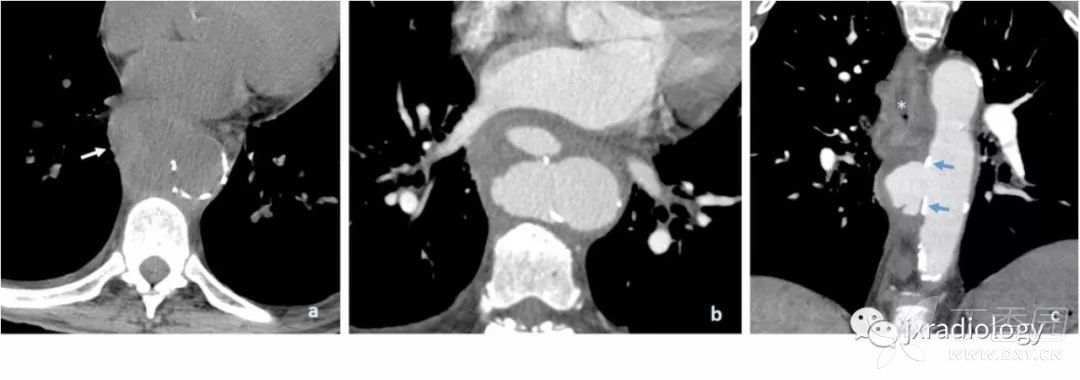

平扫CT上显示广泛的动脉粥样硬化通常是PAU患者的一个特征。注射对比剂后,主动脉壁出现不规则边缘和围绕溃疡基底部的内膜钙化提示PAU诊断( 图13 )。

图13:在轴位非增强CT显示主动脉后壁广泛的动脉粥样硬化(a图中箭头)。注射对比剂后,没有内膜瓣的情况下主动脉的后囊袋状突起(b和c图的星号)。

当发生破裂时,很难区分破裂的是动脉瘤或复杂的动脉粥样硬化性溃疡。在这两种情况下,都需要立即进行手术治疗。非穿透性溃疡一般限于内膜并常常无症状( 图14 )。